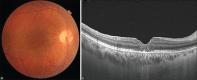

The occurrence of full thickness macular hole in Coats' disease is extremely rare. The purpose of this case report is to report pars plana vitrectomy for the treatment of full thickness macular hole in a patient with adult onset Coats disease. A young male presented with decreased vision in his right eye because of full thickness macular hole. The macular hole was found to be associated with adult onset Coats' disease that was evident on ultra-wide field imaging. The patient underwent laser photocoagulation to the vascular telangiectasia followed by pars plana vitrectomy, large internal limiting membrane peeling and gas tamponade. This resulted in regression of exudation, closure of macular hole and improvement in vision. Coats disease of adult onset can present with decreased vision because of full thickness macular hole. Vitrectomy with internal limiting membrane peeling can result in excellent visual outcome.